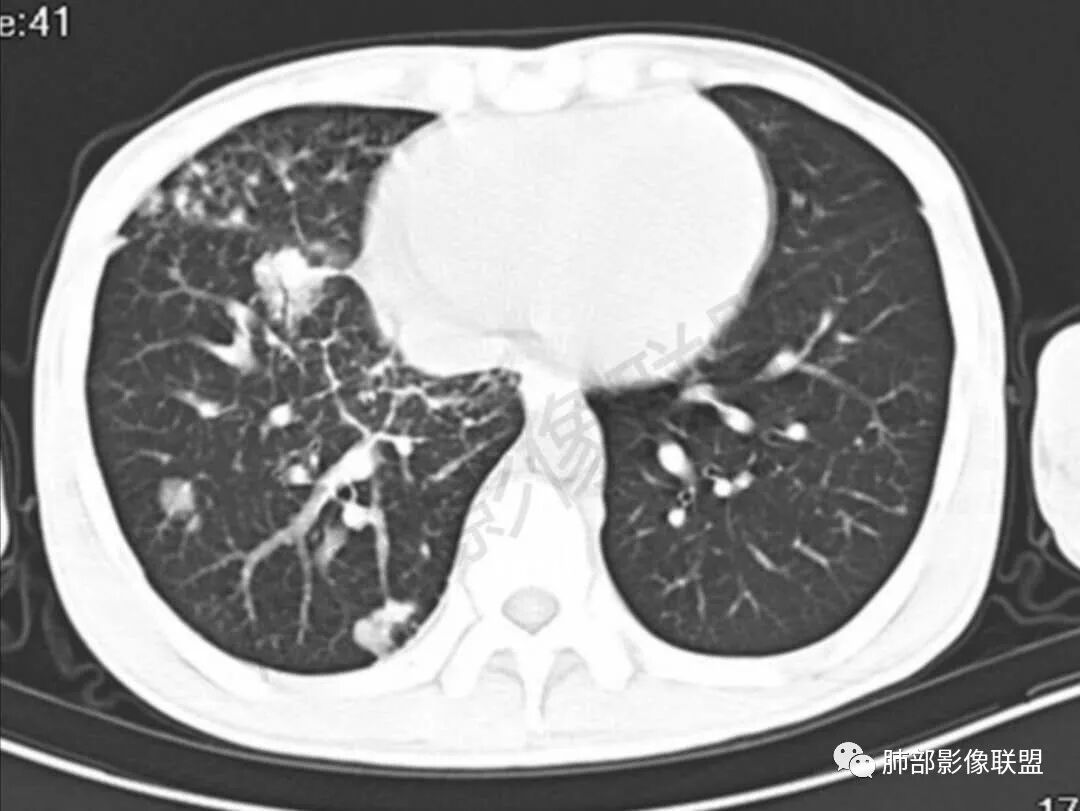

3、影像表现:双肺散在斑片影及结节影,部分结节内可见血管穿行,斑片影沿支气管血管束分布,近胸膜侧病变收缩不明显。部分中央淋巴间质增厚,小叶间隔增厚。病灶内支气管穿行,部分支气管略扩张。局部小结节呈串珠样改变。纵隔、肺门区、锁骨上及腋窝淋淋巴结肿大,部分有融合。心腔低密度。脾大。

2.双肺多发片影及结节影,边界可分辨,右肺中上叶较为密集,没有胸膜下分布优势。病灶实性密度为主,未见钙化及液化。

3.右肺较多微小结节,密度较为浅淡,部分沿血管束分布,未见沿小叶间隔及叶间裂分布结节影,未见典型的终末气道树芽。

5.双肺门及纵隔淋巴结显著增大,这改变相当显眼。这里强调“双肺门”及“多发”!

增大的淋巴结密度偏低且均匀。此外患者有体表淋巴结增大。

淋巴瘤肺部浸润表现多样,多发结节影是其最常出现的影像学改变,尤其是霍奇金病。

2.右肺多发微小结节影,部分沿血管束分布,尽管未见小叶间隔改变,但双肺门淋巴结增大确实应当首先排除结节病,但经验上说,结节病的增大淋巴结密度往往较高、较密实,边界往往清楚,“独立性”很强,绝无“融合之嫌”!此外,较少出现贫血、脾大,临床表现也往往较轻微。

3.双肺多发结节影,没有明显的新旧不等,没有钙化,微小结节影密度偏低,边缘不够僵硬锐利;病灶区域穿行支气管显示良好,未见壁增厚及管腔狭窄,加之病灶如此广泛,病灶未见收缩、肺叶体积未见缩小,结核中毒症状不明显等等都不支持结核。

双肺门、纵隔及全身浅表淋巴结都增大,对于结核病而言还是少见一些。